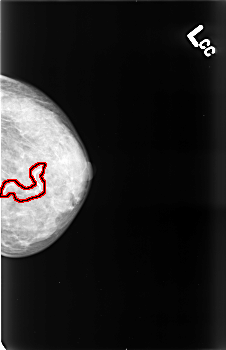

FILE: B_3428_1.LEFT_CC.OVERLAY

TOTAL_ABNORMALITIES 1

ABNORMALITY 1

LESION_TYPE CALCIFICATION TYPE VASCULAR DISTRIBUTION N/A

ASSESSMENT 2

SUBTLETY 5

PATHOLOGY BENIGN_WITHOUT_CALLBACK

TOTAL_OUTLINES 2

BOUNDARY